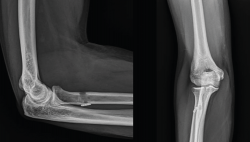

En cuanto a las pruebas de imagen, las radiografías simples suelen ser normales en todas las lesiones del bíceps distal y no añaden información más allá de cambios discretos por reacción perióstica en la tuberosidad bicipital y, en casos muy poco frecuentes, avulsión de un fragmento óseo(19).

Figura 3. Imagen lateral de una rotura crónica del tendón del bíceps distal con masa muscular ascendida y adelgazamiento del perímetro distal del brazo.